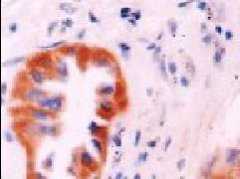

乳腺癌